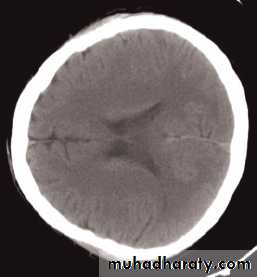

Computed tomography of the brain

• A routine CT examination of the brain involves making 20–30 axial sections.

• The axial plane is the routine projection but computer reconstructions can be made from the axial sections, which then provide images in the coronal or sagittal planes

• The window settings are selected for the brain and are also altered to show the bones

The cardinal signs of an abnormality on a CT scan are:

• Abnormal tissue density• Mass effect

• Enlargement of the ventricles.

Abnormal tissue density

• Abnormal tissue may be of higher or lower density than the normal surrounding brain.• High density is seen with recent haemorrhage, calcified lesions, and areas of contrast enhancement

• Low density is usually due to neoplasms or infarcts, or to oedema, which commonly surrounds neoplasms, infarcts, haemorrhages and areas of inflammation.